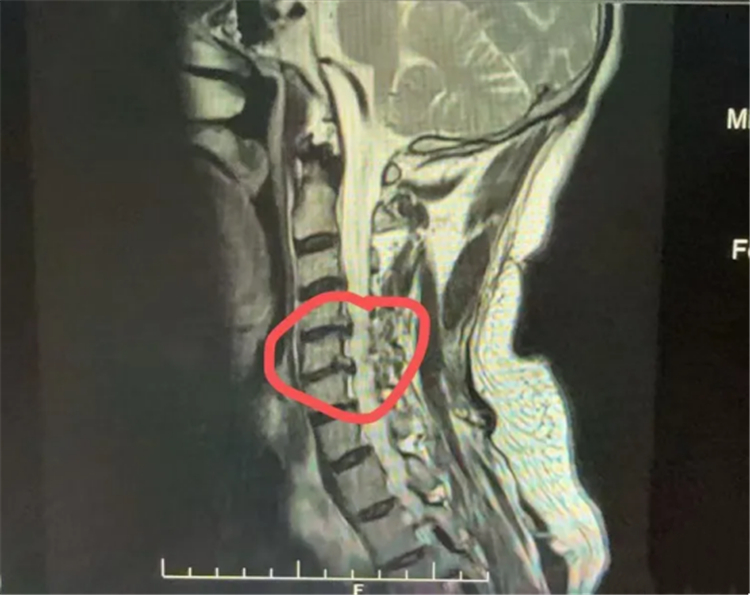

患者术前影像资料

经同乡推荐,伍大叔来到长沙泰和医院脊柱外科求诊。科室主任、留日博士宋西正教授接诊后,经详细检查确诊其为“双节段椎间盘突出合并脊髓型颈椎病”。宋西正教授介绍,脊髓型颈椎病是颈椎病中最严重的类型,源于颈椎病变压迫脊髓神经,可能导致四肢无力、行走不稳,甚至瘫痪,必须尽早手术干预。